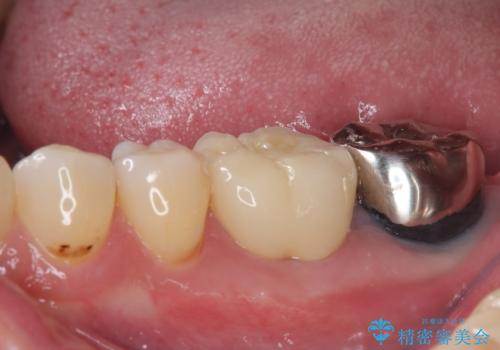

- 下顎大臼歯が噛めないほどの痛みを感じるとのことで来院された患者様です。

レントゲン写真などで診査を行ったところ、不適合な詰め物の周りから炎症が波及し、神経組織が壊死していると診断されました。

まずは根管治療を行い、症状が消退したことを確認してオールセラミッククラウンにて補綴治療を行うこととしました。